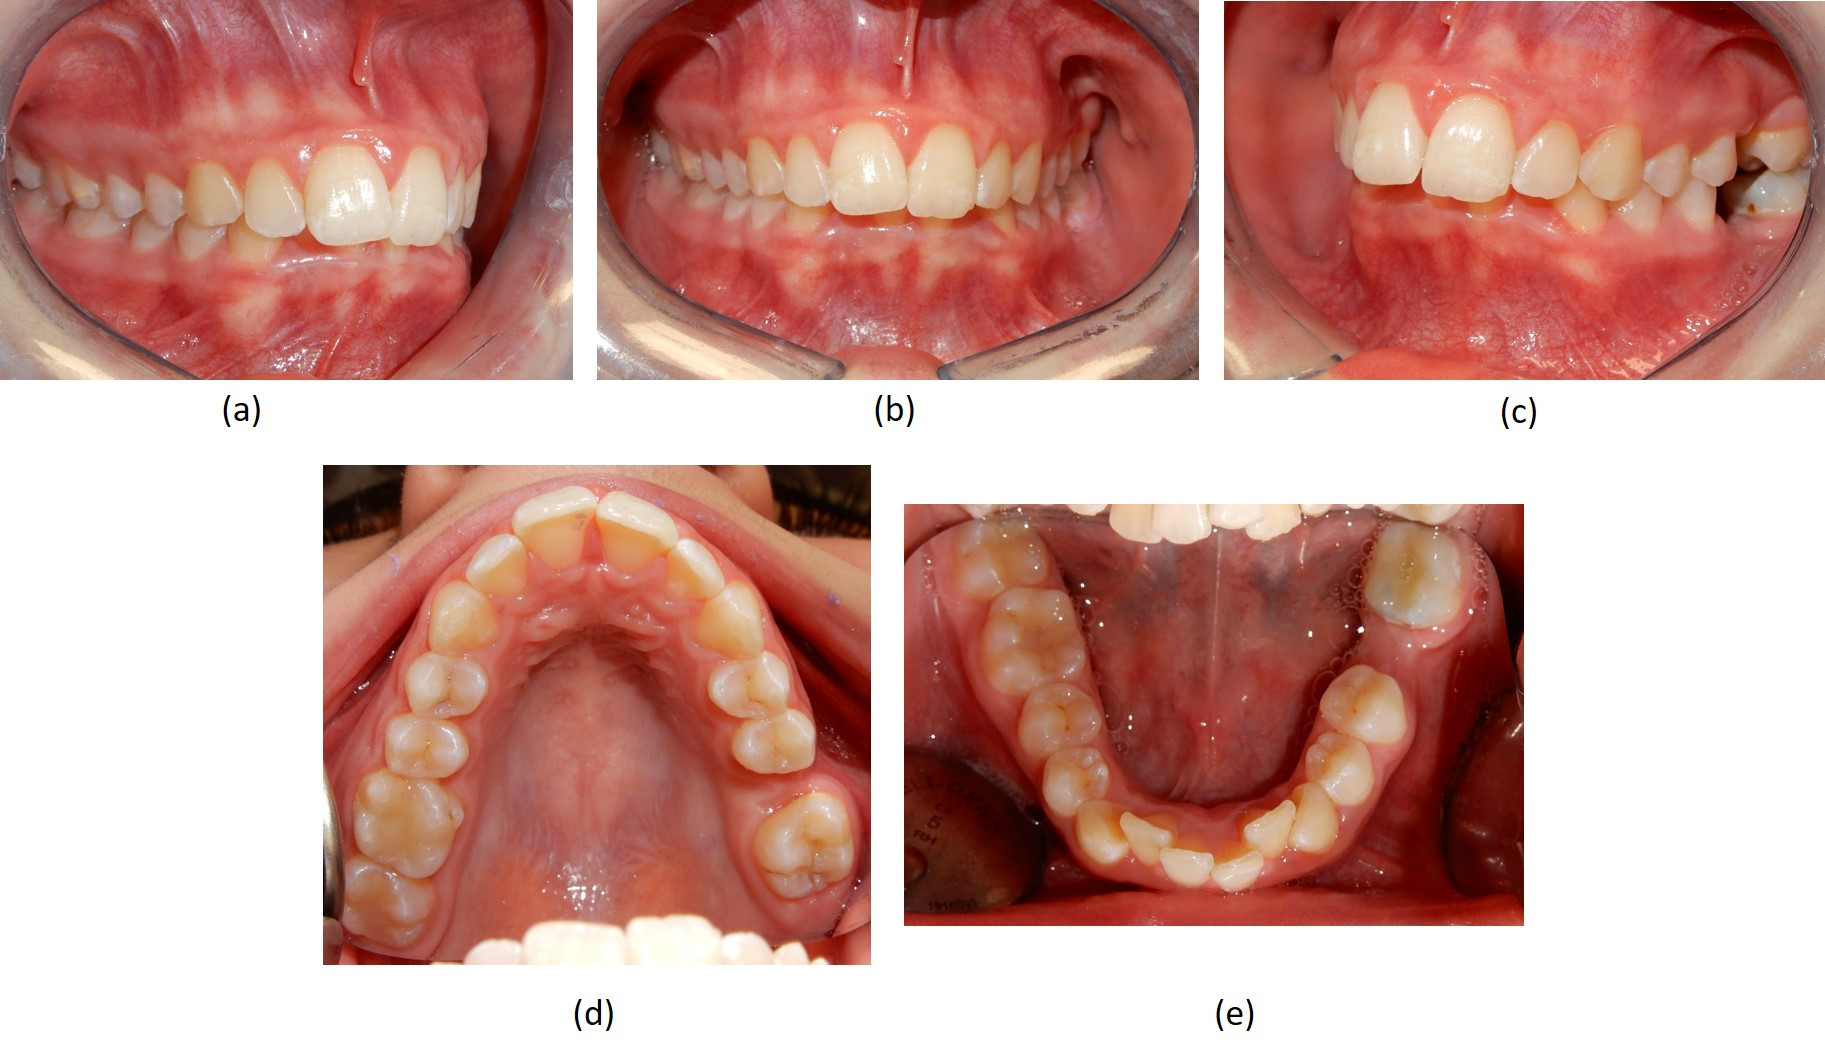

Fotografie intraorali  pre-trattamento

Fig. 3 Fotografie intraorali  pre-trattamento. (a) visione laterale destra; (b) visione frontale con morso profondo; (c) assenza dei due primi molari sul lato sinistro; (d) visione occlusale superiore che mostra l'assenza del primo molare sinistro; (e) visione occlusale inferiore che mostra sul lato sinistro l'assenza del primo molare e l'affollamento moderato degli incisivi